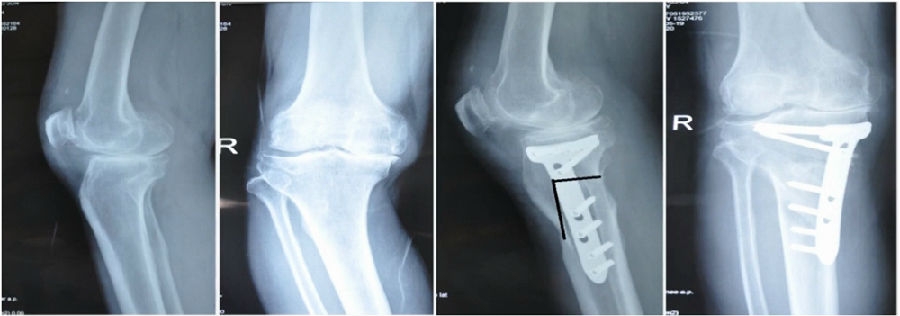

典型病例,男性,57岁,农民,左膝疼痛3年。

术前

术前影像资料

术前规划:

①关节内截骨,内外侧平台平行。

关节内截骨

②再次确定下肢力线。

确定力线

③关节外截骨。

关节外截骨

术中先打克氏针确定截骨方向,先做关节内截骨,截完后测量下肢力线,发现并没达到术前设计的Fujisawa点。

术中影像资料

随后用骨刀继续向前敲,做HTO内侧开放楔,截骨完成后内侧固定,并测量下肢力线,此时达到术前设计的要求。

术后检查证实达到了术前预期的手术效果,关节线达到了平行,半脱位得到矫正,同时关节线和地面水平。病人行走达到了理想的效果。

术后X线

患者术后4个月截骨愈合,膝关节稳定维持得非常好。

术后4个月